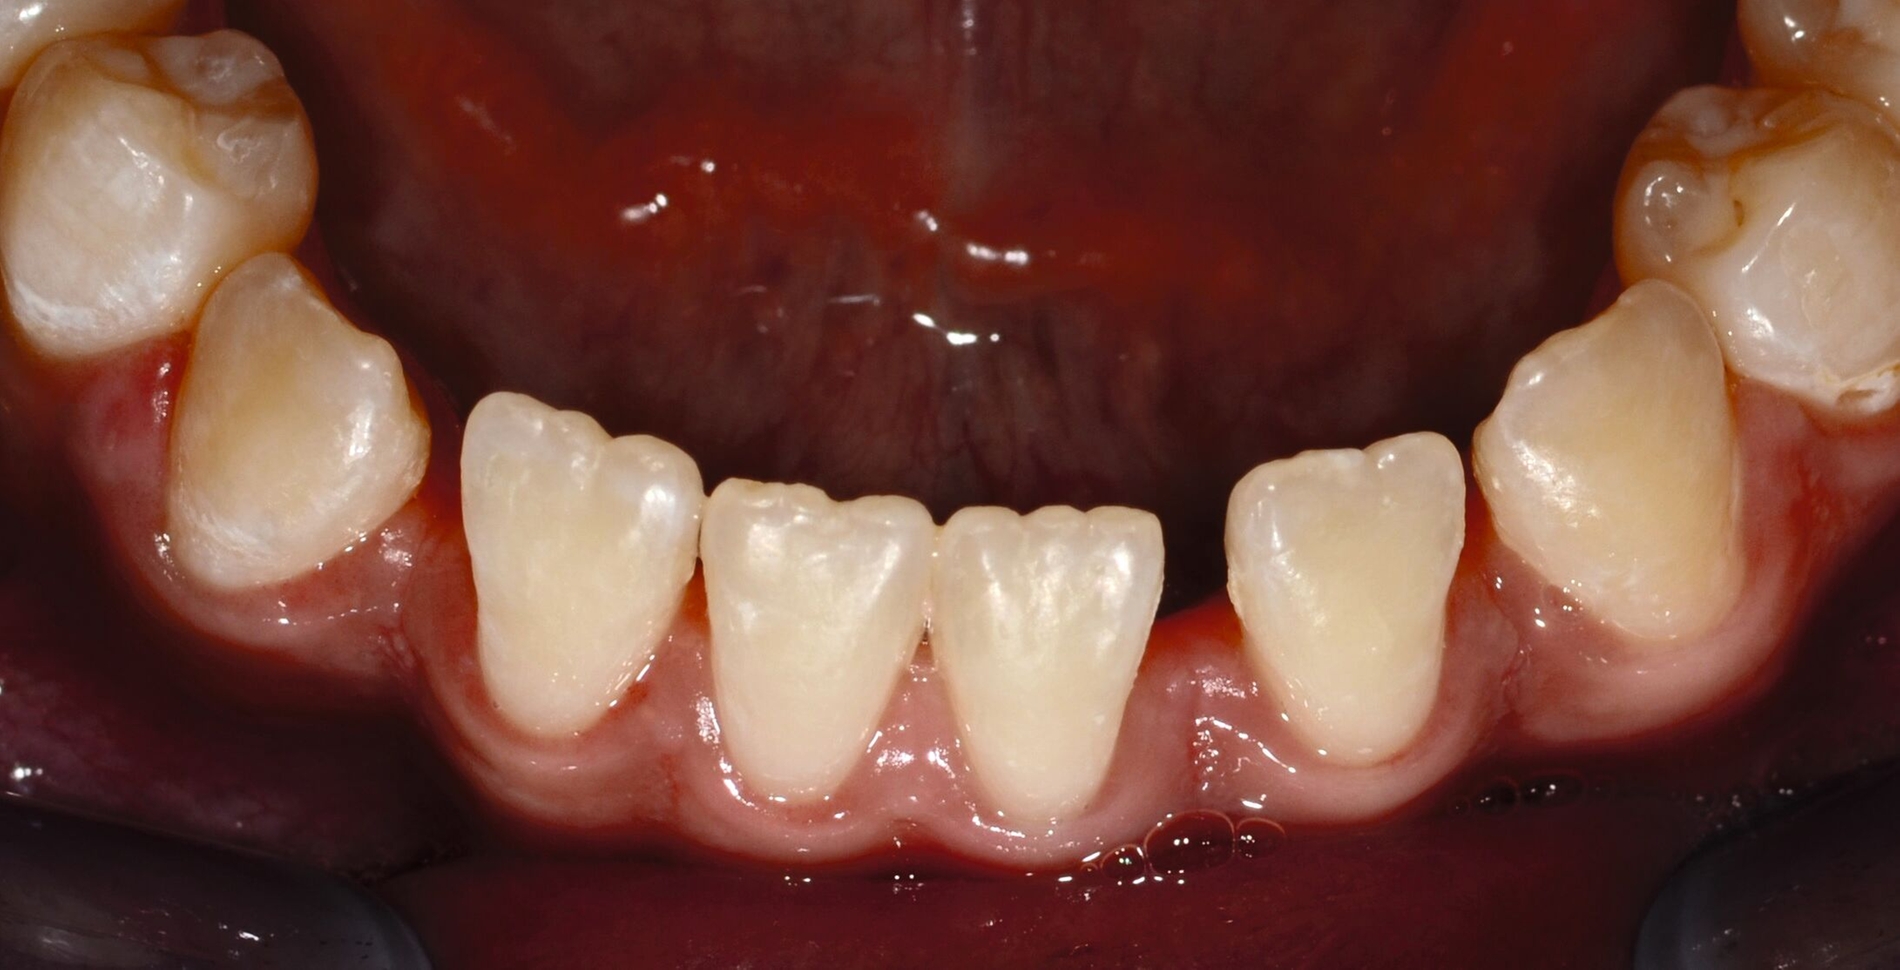

... mit Höckerersatz im Seitenzahnbereich

Für die Höckerüberkappung bedarf es eines ausreichend stabilen und abrasionsfesten Materials, das durch okklusale Kräfte belastet werden kann und die anatomische und funktionelle Rekonstruktion des Zahnes ermöglicht. Die Evidenz zur Verwendung von Kompositmaterialien bei Seitenzahnkavitäten mit Höckerersatz zeigt in mehreren Studien gute Überlebensraten [Deliperi et al., 2006; ElAziz et al., 2020; Fennis et al., 2014]. Van Nieuwenhuysen et al. [2003]berichtetenvon hohen Versagensraten sowohl bei Komposit- als auch bei Amalgamrestaurationen (30,4 Prozent beziehungsweise 28,1 Prozent). Diese Daten sind jedoch aufgrund der Verwendung älterer Kompositmaterialien als veraltet zu werten.

MERKE: Moderne Kompositmaterialien sind leistungsfähig und entsprechen den Prinzipien der minimalinvasiven Zahnmedizin. Insofern ist die Höckerrestauration mittels Komposit möglich (Abbildung 2).

Die Gruppe hat mit starkem Konsens die Empfehlung ausgesprochen, dass für Höcker-ersetzende Restaurationen insbesondere bei spezifischen Einflussfaktoren auf Zahn-, Mund- und Patientenebene (zum Beispiel eingeschränkte Compliance, schlechte Zugänglichkeit, komplexe funktionelle Rehabilitation) der Einsatz von indirekten Kompositrestaurationen erwogen werden kann.